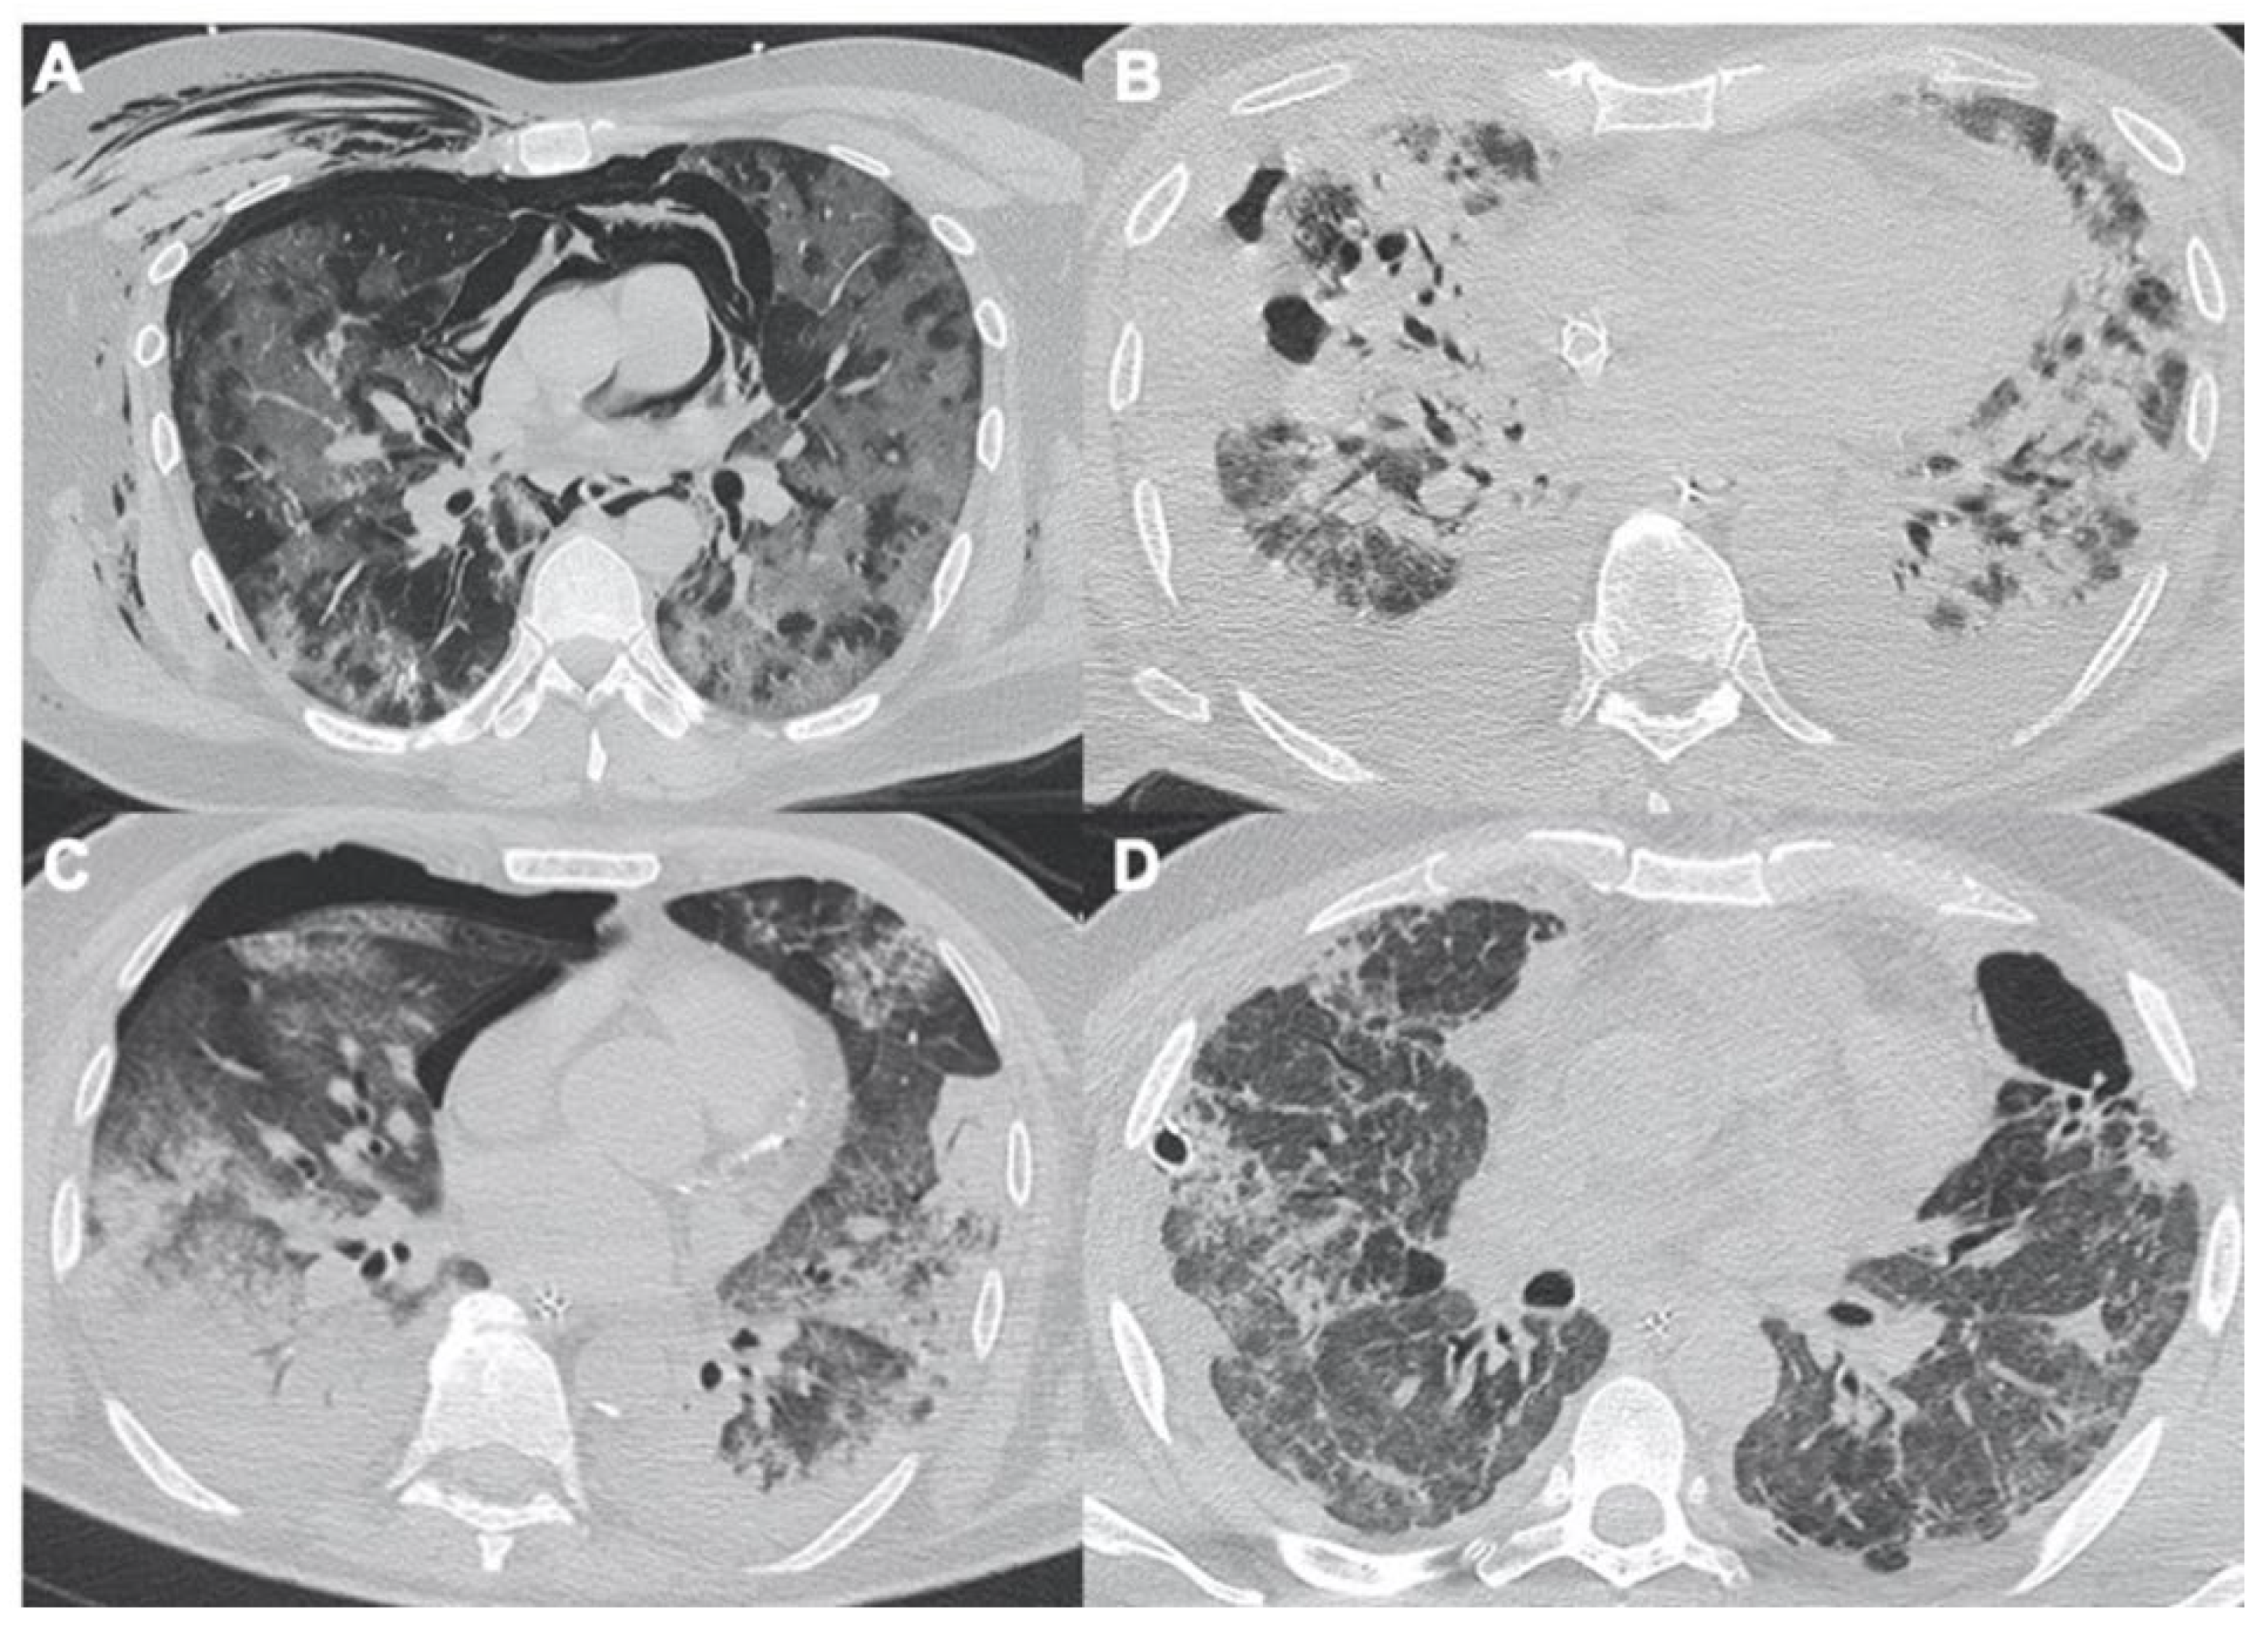

2.2. Acute Respiratory Disease Syndrome

- Ferrando, C.; Suarez-Sipmann, F.; Mellado-Artigas, R.; Hernández, M.; Gea, A.; Arruti, E.; Aldecoa, C.; Martínez-Pallí, G.; Martínez-González, M.A.; Slutsky, A.S.; et al. Clinical features, ventilatory management, and outcome of ARDS caused by COVID-19 are similar to other causes of ARDS. Intensiv. Care Med. 2020, 46, 2200–2211. [Google Scholar] [CrossRef]

- Stefanidis, K.; Moser, J.; Vlahos, I. Imaging of Diffuse Lung Disease in the Intensive Care Unit Patient. Radiol. Clin. N. Am. 2020, 58, 119–131. [Google Scholar] [CrossRef] [PubMed]

- McGuinness, G.; Zhan, C.; Rosenberg, N.; Azour, L.; Wickstrom, M.; Mason, D.M.; Thomas, K.M.; Moore, W.H. Increased Incidence of Barotrauma in Patients with COVID-19 on Invasive Mechanical Ventilation. Radiology 2020, 297, E252–E262. [Google Scholar] [CrossRef] [PubMed]